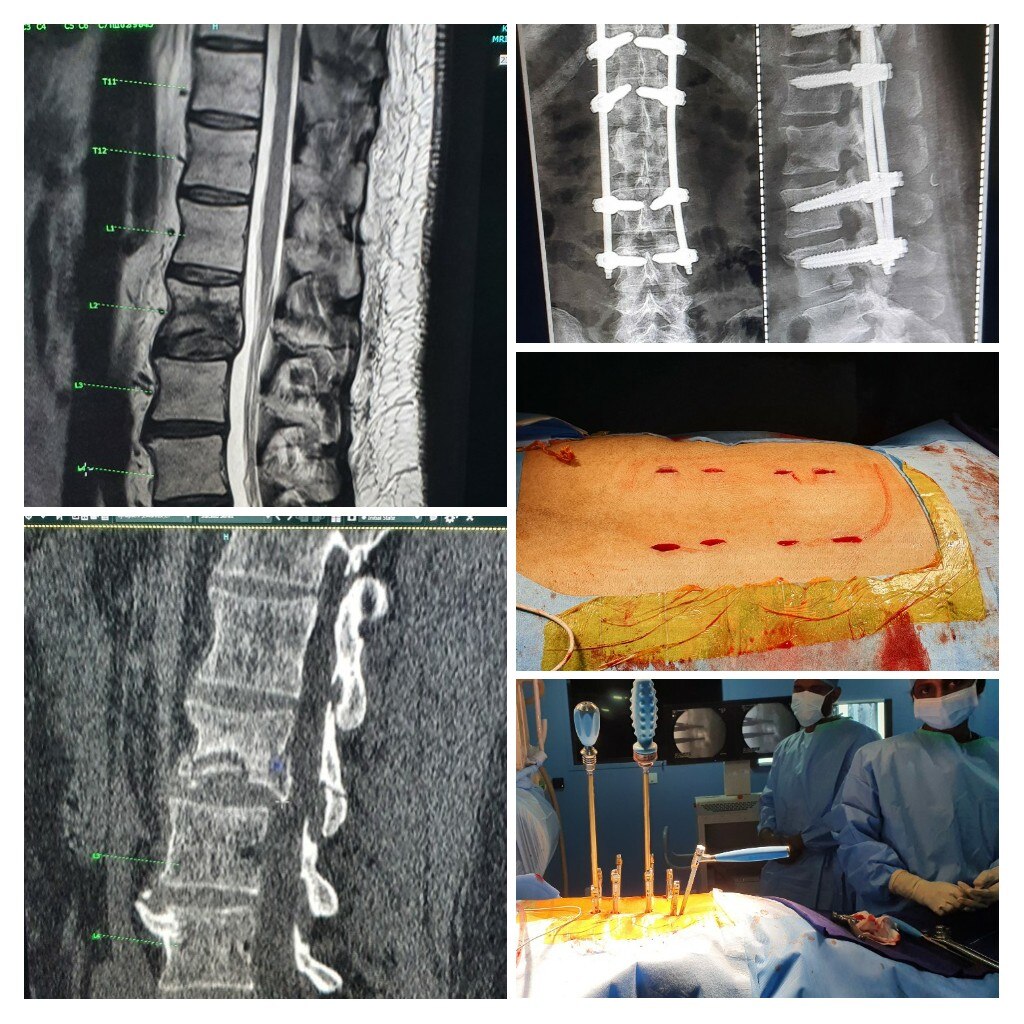

Dr Abhijit Pawar is the Best Spine Surgeon in Pune. He is the leading Minimally Invasive Spine Surgeon, Endoscopic and Spinal Deformity Surgeon, Back Pain/Neck Pain Specialist, Spine Specialist, Spine Doctor, Spine Surgeon in Baner, Balewadi, Mahalunge, Sus, Pashan and Pune. Dr Abhijit Pawar is a Senior Spine Surgeon also practices at Kokilaben Dhirubhai Ambani Hospital Mumbai(KDAH). He specializes in minimally invasive spine surgery, endoscopic spine surgery and scoliosis surgery. He is the pioneer of 3d Navigation guided (O-Arm) spine and scoliosis surgery in India. He has done extensive research in the field of spine surgery and published about 25 articles and book chapters in international spine journals. Till date he has successfully performed about 3500 successful spine surgeries at KDAH. Dr Pawar is an avid trekker and marathoner and has successfully scaled several peaks in India in the last 5 years. He is an active member of rotary club of Mumbai. With the association of rotary club and KDAH they treat needy children with scoliosis at affordable costs.